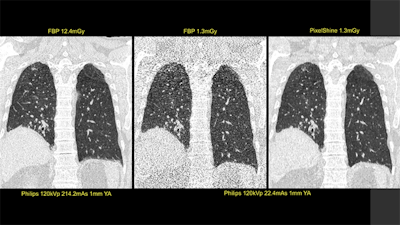

First image: Standard, high-dose CT at 12.4 mGy. Second image: Ultralowdose CT at 1.3 mGy. Third image: AI-enhanced ultralow-dose CT at 1.3 mGy. Diagnostic image quality between the first and third images was rated as comparable by independent radiologists, despite a significant dose reduction of 11.1 mGy. The second image is noisy and nondiagnostic. Image courtesy of Algomedica and Dr. Hugh Harvey, Kheiron Medical.